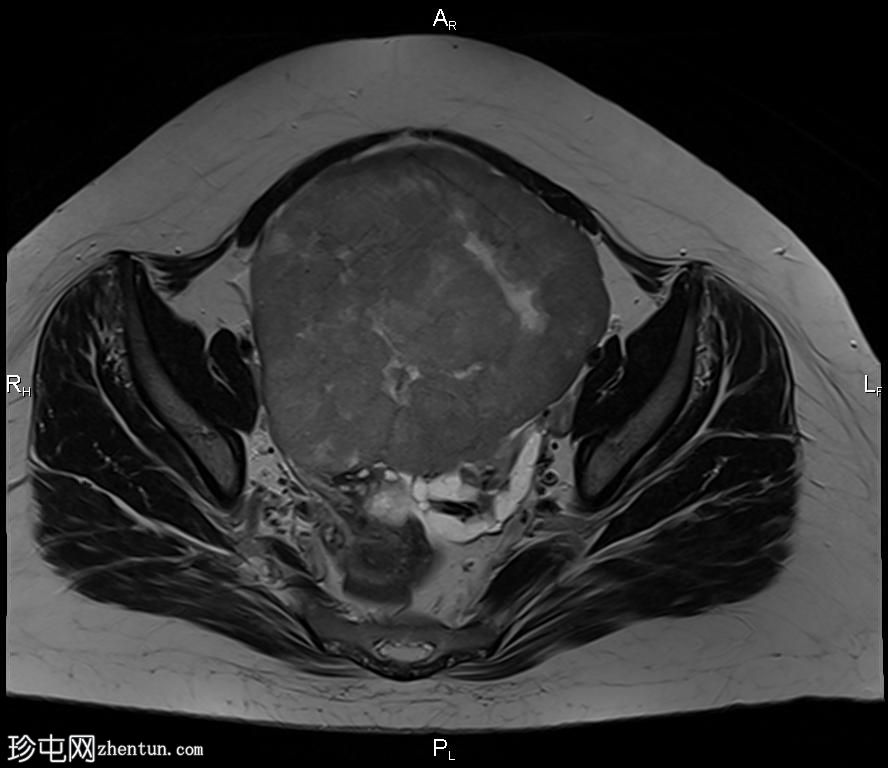

冠状位

T2

盆腔内可见一巨大多分叶实性肿块,内部有隔膜,T2WI信号不均匀,T1WI信号不均匀,呈低信号。肿块内散在分布囊性/坏死性病变。

肿块外可见子宫和右侧卵巢,肿块似源自左侧卵巢。该肿块压迫膀胱和两侧远端输尿管,并导致肠管和血管结构移位,但无侵袭或包裹征象。

造影后,肿块呈不均匀强化,隔膜强化。

远端髂腹旁和两侧髂骨旁区域可见少量肿大淋巴结。